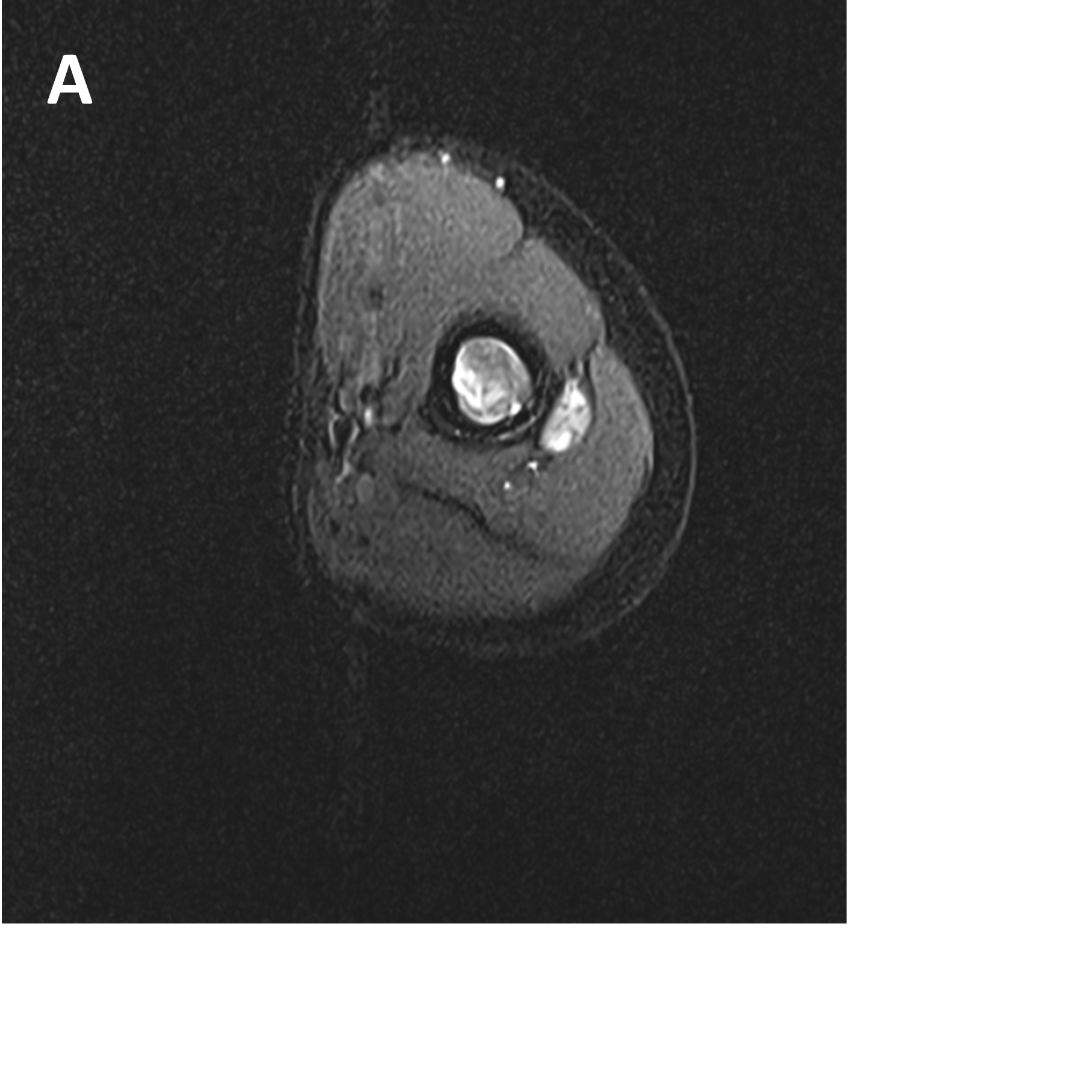

- B 1 : Tract of previous intramedullary nail seen in shaft of humerus, along with mild diffuse cortical thickening.

- B 2 : Volume loss with fatty atrophy of brachioradialis, supinator, extensor carpi radialis longus and brevis muscles ,due to chronic denervation changes.